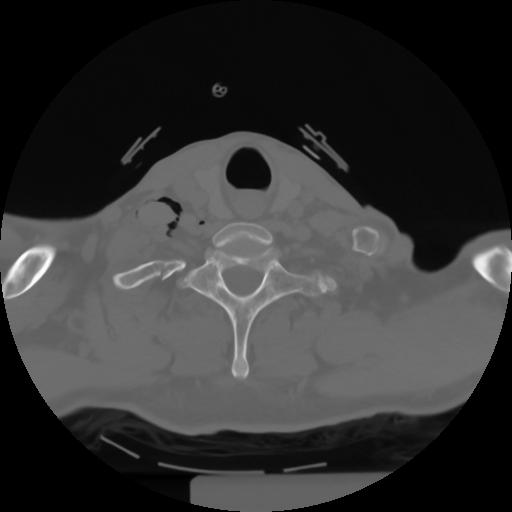

10 P.BLANDAS,,Axial,2.0,P.BLANDAS,,